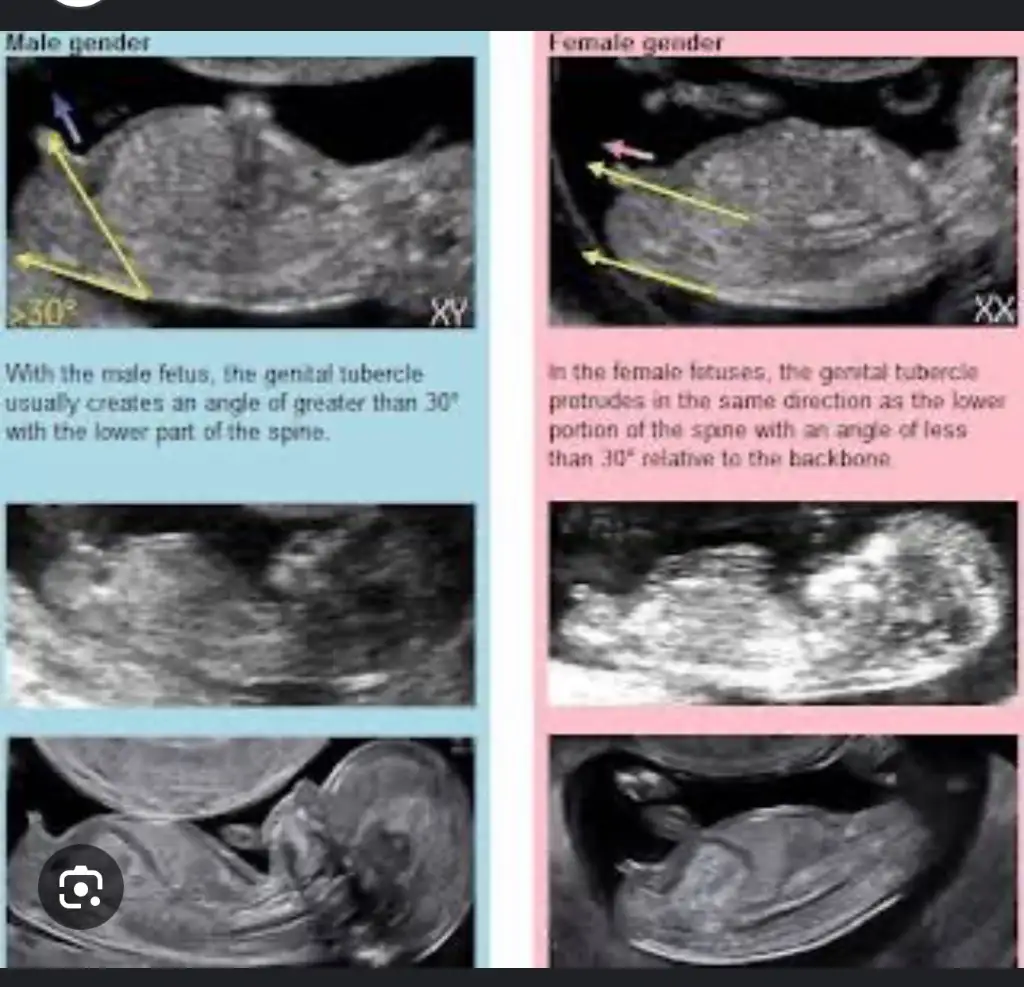

Bana da yorum yapar mısınız ? Arada gibi sanki erkeğin 1. Fotosuna da benziyor kızın 3.fotosuna da ben anlayamadımİnternetten nub teorisi diye arastır sende tahminde bulunabilirsin :)

Nub nasil oluyorki? Hala anlayamadim. 30 derecelik aciya gore dimi? Ben en son 10+2de ultrason muayenesinde oldum. Bi fark olur mu 2 haftada?Kese şekliyle ilgisi yok bence ama nub doğru